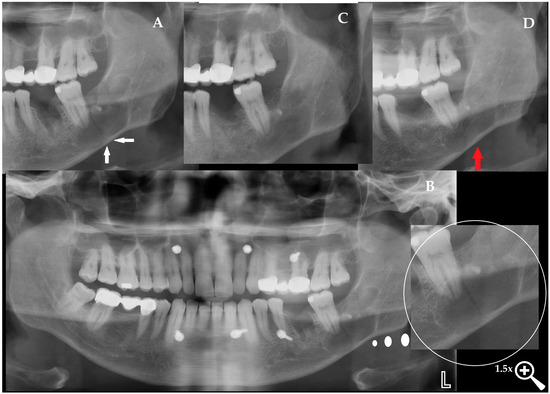

Mandibular Brown Tumor as a Result of Secondary Hyperparathyroidism—Radiological and Clinical Pitfalls and Dilemmas

Brown tumors (BTs) are rare osteolytic lesions that typically occur in association with primary or secondary hyperparathyroidism (PHP and SHP). Excessive secretion of parathyroid hormone induces increased bone resorption, resulting in lesions characterized by fibrosis, vascularization, and hemosiderin deposition. The most common sites [...] Read more.

Brown tumors (BTs) are rare osteolytic lesions that typically occur in association with primary or secondary hyperparathyroidism (PHP and SHP). Excessive secretion of parathyroid hormone induces increased bone resorption, resulting in lesions characterized by fibrosis, vascularization, and hemosiderin deposition. The most common sites include the jaws, ribs, pelvis, and long bones. Clinical manifestations may involve pain, swelling, or pathological fractures. We present the case of a mandibular BT in a 48-year-old female with chronic renal failure and secondary hyperparathyroidism. The patient exhibited progressive mandibular swelling with radiological features resembling an aggressive odontogenic or malignant lesion. Laboratory analysis confirmed markedly elevated parathyroid hormone levels, while scintigraphy demonstrated increased focal uptake in the mandible and ribs. Histopathological evaluation revealed multinucleated giant cells within a fibrous stroma, consistent with BT. Despite initiation of systemic endocrine therapy, the lesion continued to enlarge, necessitating complete surgical excision of the mandibular mass. This case underscores the diagnostic dilemmas of mandibular BT, which may closely mimic aggressive jaw pathologies. Importantly, while many BTs regress after systemic management of hyperparathyroidism, this case illustrates that surgical excision may be unavoidable in patients with unstable systemic status or progressive local disease. Comprehensive clinical, radiological, laboratory, and histopathological evaluation remains essential to ensure timely diagnosis and appropriate treatment. Full article

Figure 1